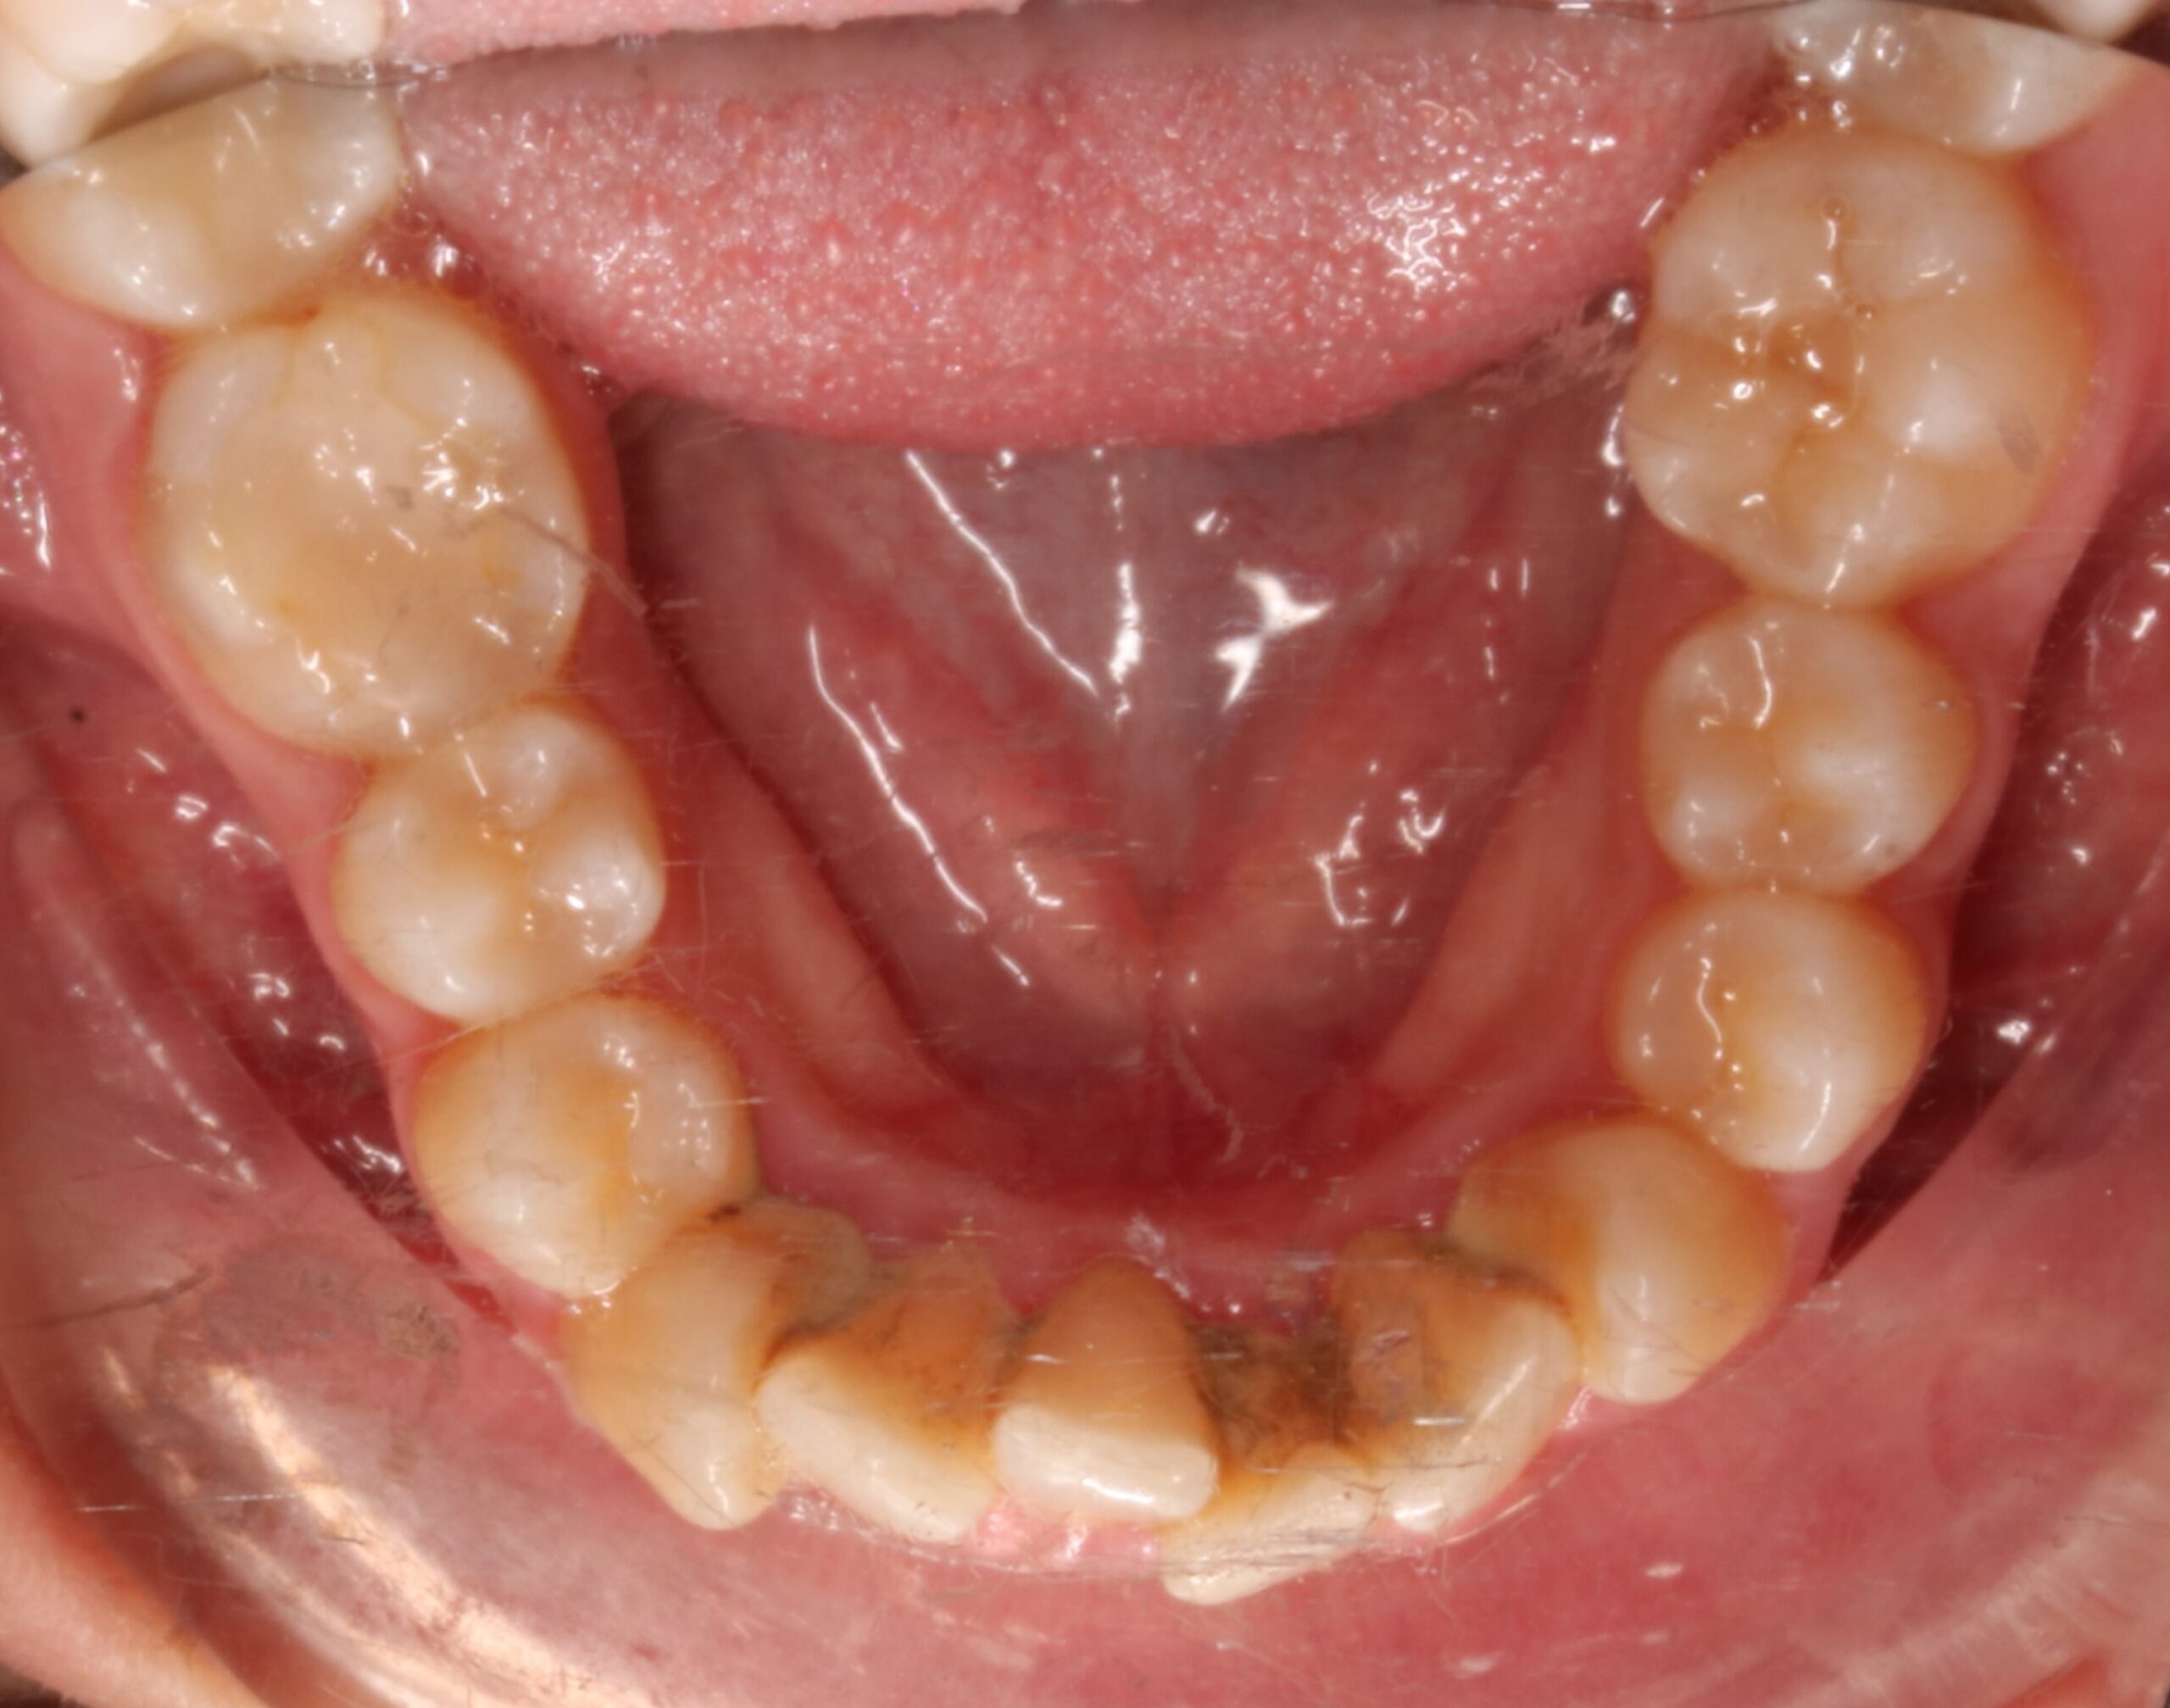

Como principal escollo, nos encontramos con una activa enfermedad periodontal y una deficiente higiene oral. También hay otros problemas secundarios que no hay que desdeñar: apiñamiento inferior con Bolton; leve apiñamiento anterosuperior; malposición de los cordales 48 y 38; rotación del 23; ligera clase II en el lado derecho entre otros. De primera hora se le comunicó a la paciente que antes de empezar el tratamiento de ortodoncia era necesario realizarse de periodoncia, y que después el/la profesional de esta disciplina, nos confirmara que podíamos empezar nuestro trabajo. También, avisamos de la importancia, de que durante el tratamiento, era necesario acudir al periodoncista cada 2 meses y mejorar la higiene oral.

APIÑAMIENTO INFERIOR IPR 42-32 (BOLTON) + PROTRUSIÓN INERIOR

FOTOGRAFÍAS DE INTERÉS